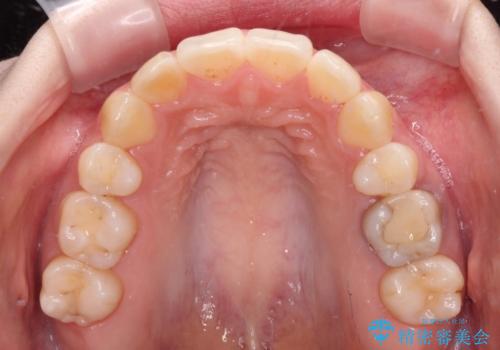

- 高校生の時に矯正治療を行ったものの、後取りをしてしまったとのことで来院された患者様です。

マウスピースでもワイヤー矯正でも対応可能でしたが、再度ワイヤーは装着したくないとのことでインビザラインにて矯正治療を行うこととしました。

舌の突出癖が原因で後戻りをしたため、舌のトレーニングをしっかりと行っていただき、口元の突出感を改善することができました。

インビザラインの装着時間が守れず、1年強で終わる予定でしたが、4年間を要することとなりました。